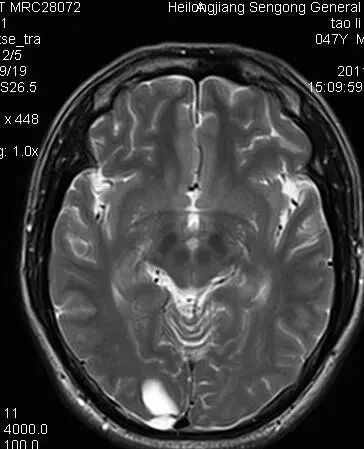

人工智能在医学中的应用目前是一个热门的话题,医学影像图像如MRI的肿瘤等病变部位检测和识别对于诊断的自动化,提供优质的治疗具有重要的意义。

肿瘤检测